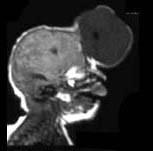

问题 根据MRI表现,考虑何种疾病是 ( )

选项 A、大脑导水管狭窄 B、脑彭出 C、Arnold-Chiari畸形 D、颅底凹陷症 E、Dandy-Walker综合征

答案 B